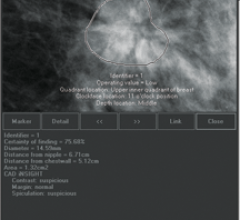

Researchers have found that digital breast tomosynthesis (DBT) led to reduced recall rates and an increase in cancer detection in a large breast cancer screening program.

Despite decades of progress in breast imaging, one challenge continues to test even the most skilled radiologists ...